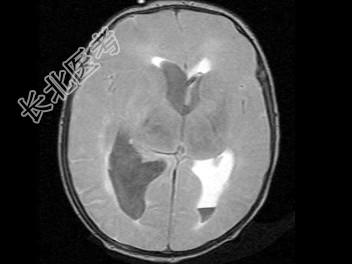

- 单项选择题男,刚满月, 突然发现不进食,昏睡, 无家族遗传病史,结合图像, 最可能的诊断是 ( )

A、脑膜炎

B、脑出血

C、脑脓肿

D、颅内动脉瘤

E、脑梗死